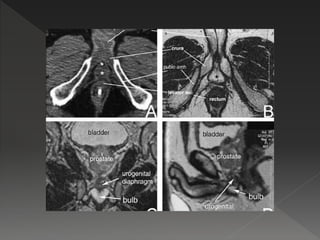

 Erectile dysfunction is a common complication following RT

for prostate cancer. Rates are

› 24% after brachytherapy alone

› 40% after brachy + EBRT

› 45% after EBRT alone

› 66% after nerve sparing –RP

› 75% after non-nerve sparing RP

› 87% for cryosurgery

 Time course – days to years, then evolves gradually

 Additive effect of age, diabetes, hypertension, smoking

 It is prudent to keep dose to

95% of penile bulb volume

<50Gy. D70 < 70Gy, D90 <

50Gy

 Its acknowledged that penile

bulb may not be the critical

component of the erectile

apparatus, but is used as a

surrogate.